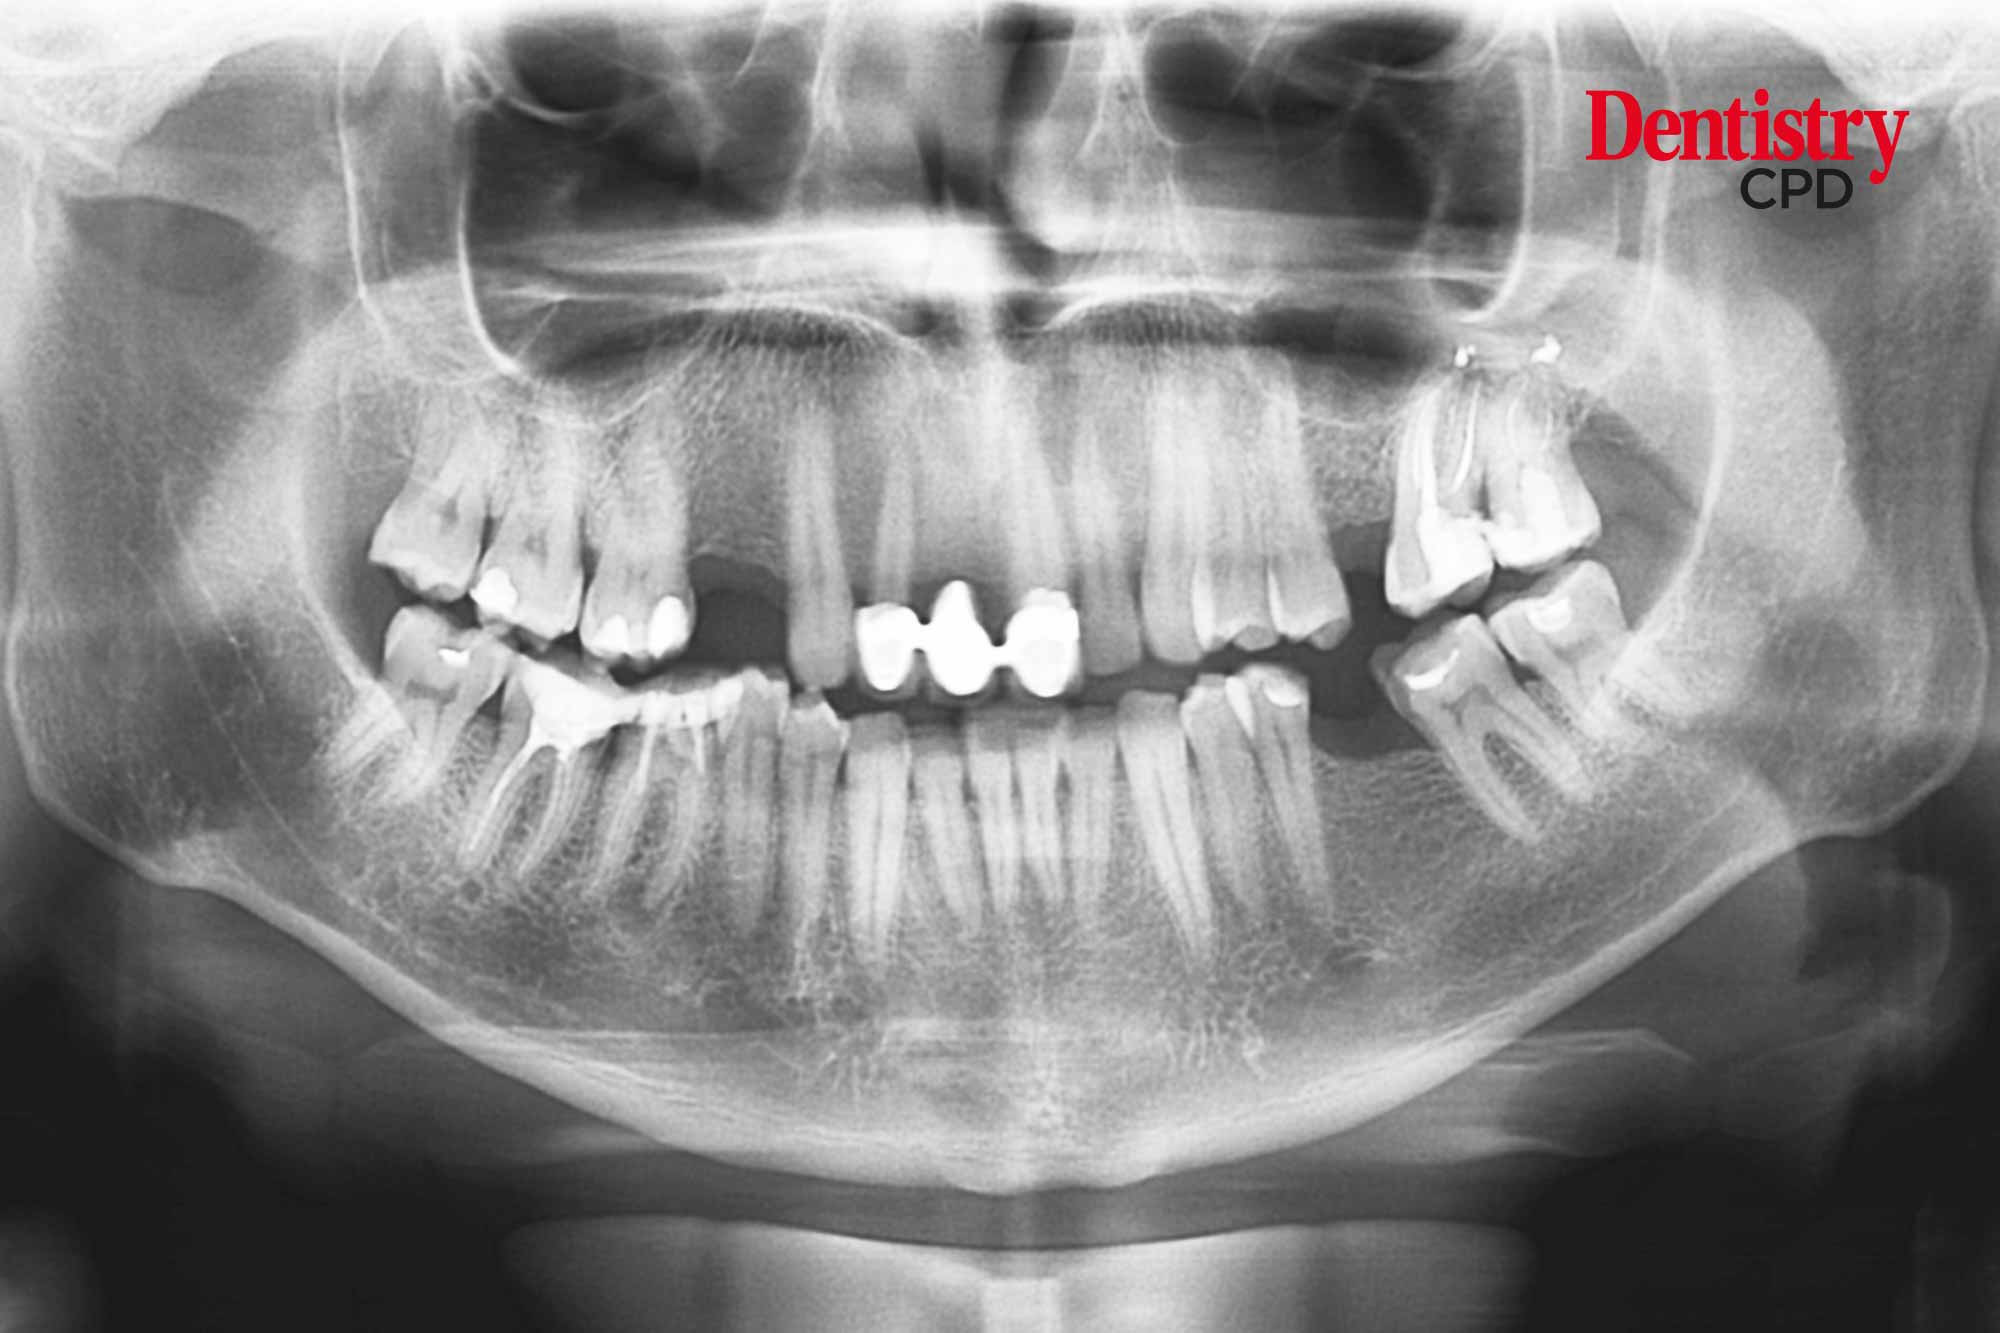

Dentistry CPD Dental radiography safe use of Xray equipment Dental Radiography Regulations Uk The faculty of general dental practice (uk)'s selection criteria for dental radiography, the leading text on indications for. The update has come after the implementation of the revised. They both form part of the health and safety at work act. The faculty of general dental practice (fgdp (uk)) has updated its text on radiography in dentistry. Although dental radiography delivers. Dental Radiography Regulations Uk.